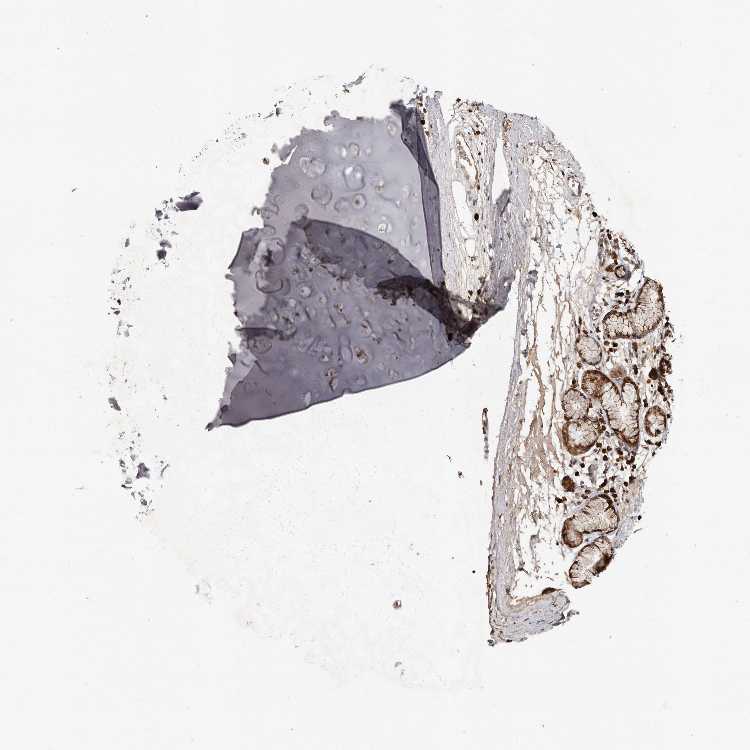

ADIPOSE TISSUE - Antibody stainingi

Antibody staining in the annotated cell types in the current human tissue is reported as not detected, low, medium, or high, based on conventional immunohistochemistry profiling in selected tissues. This score is based on the combination of the staining intensity and fraction of stained cells.

Each image is clickable and will lead to virtual microscopy that enables deeper exploration of all samples and also displays staining intensity scores, fraction scores and subcellular localization as well as patient and tissue information for each sample.

Antibody HPA029505Antibody HPA029506

Adipocytes LowNot detected